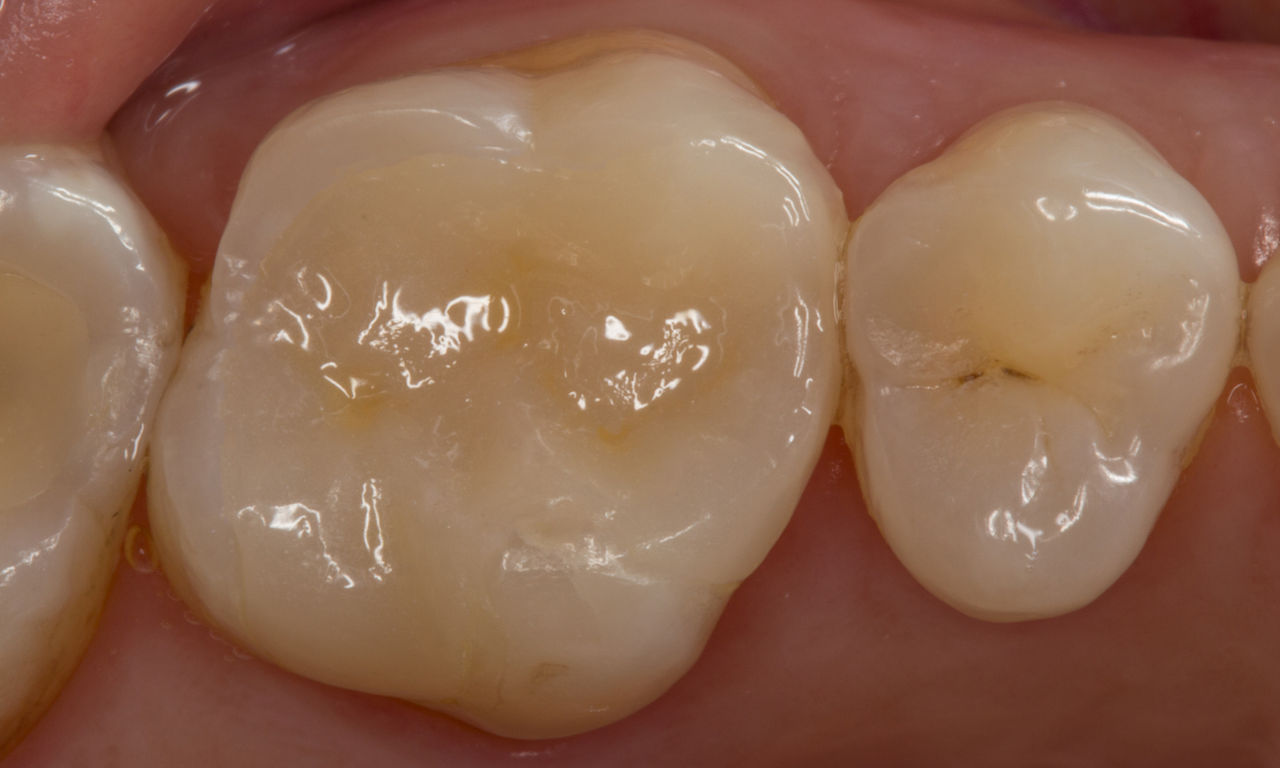

Lower second molar chairside restoration

A partial CEREC Tessera crown

A lower second molar with sensitivity presented with cracks as well as an extensive Class I composite restoration on the buccal surface. According to the minimally invasive concept a CAD/CAM partial crown was planned, fabricated and bonded using CEREC Tessera in a single visit.

Before: Failed amalgam restoration needing replacement. Patient complaining of sensitivity and tooth presenting multiple cracks.

After: Chairside CAD/CAM partial crown restoration fabricated with CEREC Tessera Advanced Lithium-Disilicate glass ceramic.

Dr. Carlos Eduardo Sabrosa

Rio de Janeiro, Brasil